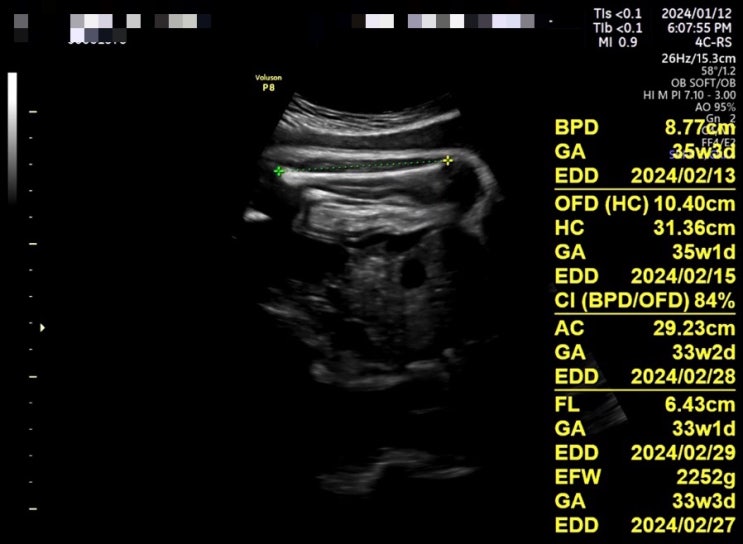

안녕하세요. 서정입니다 '◡' 금요일 정기검진 때 측정된 아기 크기를 앱에 입력해 봤어요 열달...